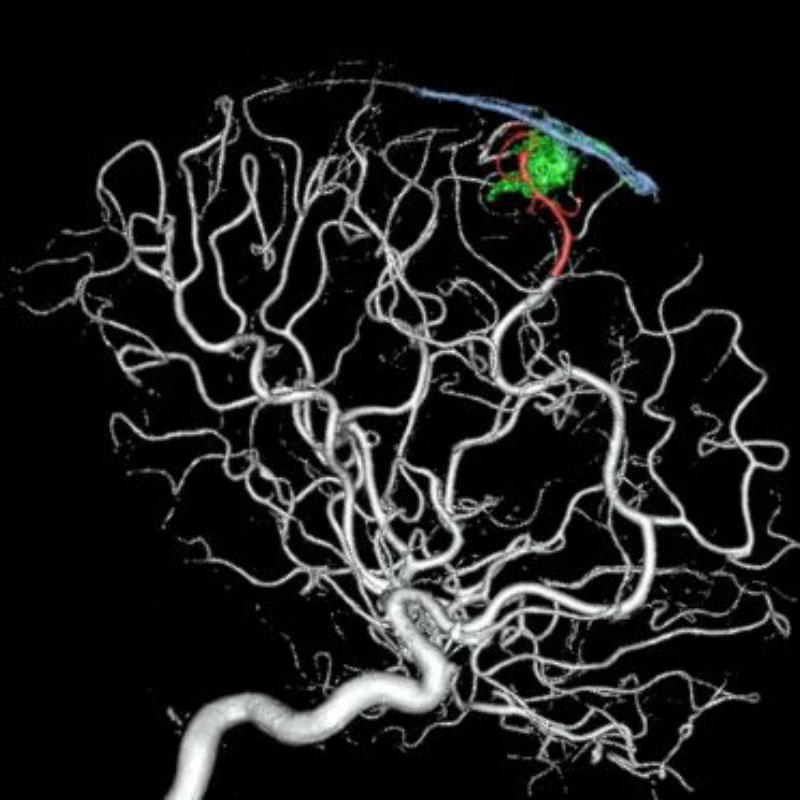

脳血管撮影

手術前

手術後